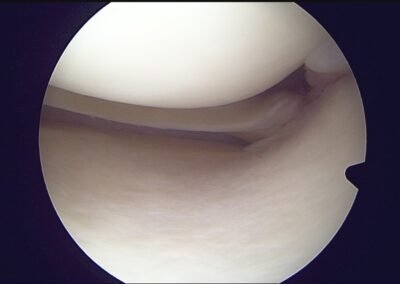

GalleryShoulder rotator cuff repair Meniscus root repair Meniscus repair Bankart repair for recurrent shoulder dislocation ACL reconstruction Machines Instruments